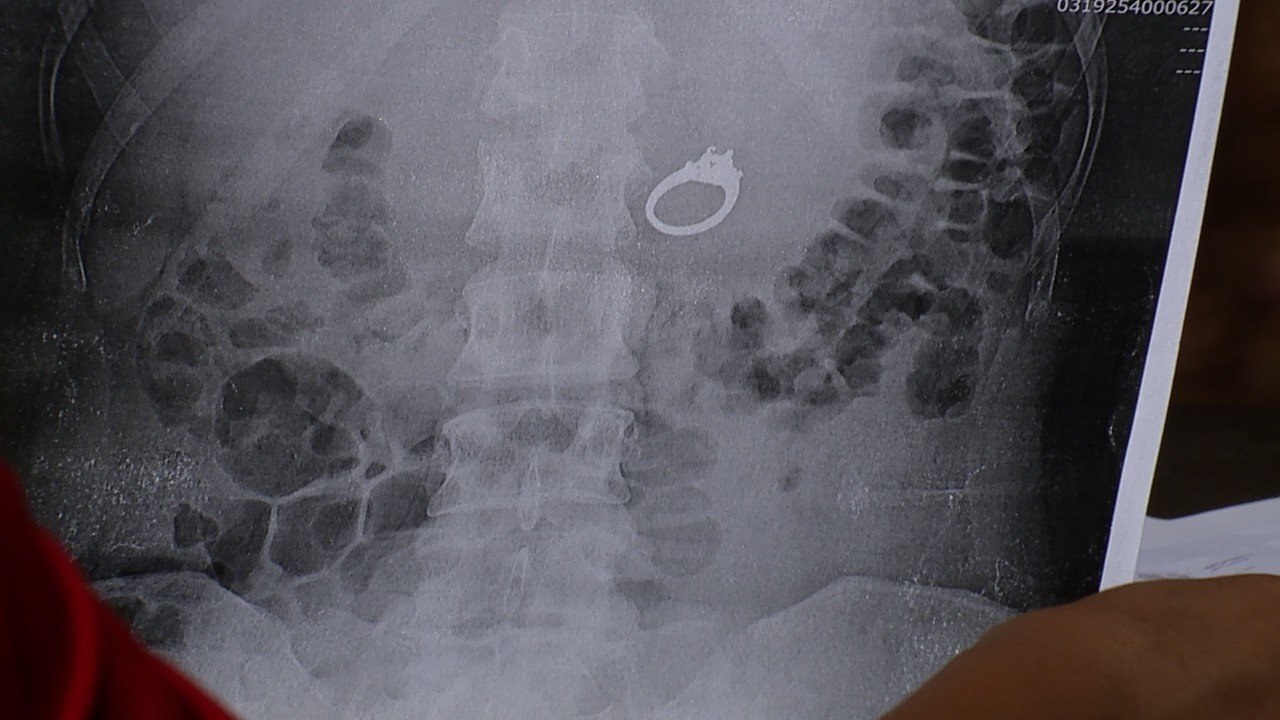

The next morning, Evans and her future husband went to Urgent Care, where they saw her X-rays. Her ring was clearly nestled right in her stomach.